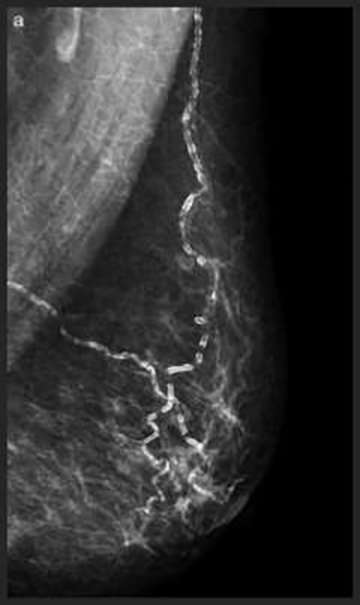

Large Rod-like Calcifications

Large Rod-like Calcifications: thick calcifications which follow the ducts, toward the nipple, secondary to secretory disease